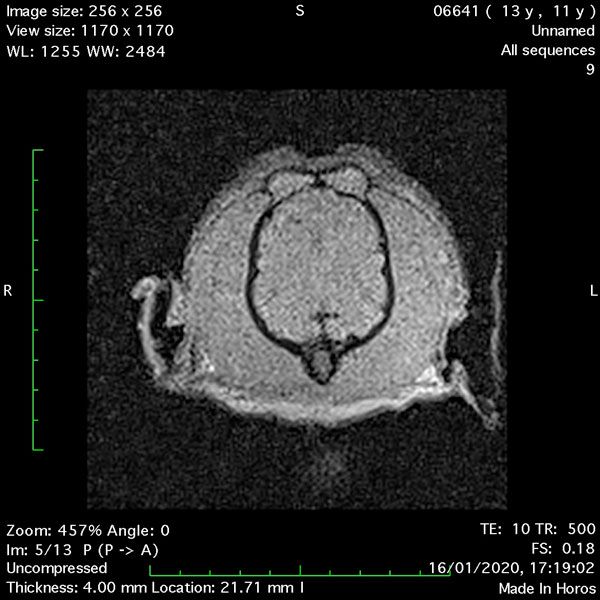

- Transverse T1 – Spin Echo T1 (Figure 1);

MRI images were viewed in DICOM format (Digital Imaging and Communications in Medicine) (Figures 1-7) and assessed in-house under the guidance of a board-certified radiologist. The series were evaluated for changes in intensity in the T1- and T2-weighted sequences (T1w and T2w, respectively). There was a 4mm x 7mm x 7mm intra-axial, wedge-shaped hyperintense reasonably-well demarcated region in the right cerebrum visible in the T2w images (Figures 2-3). This was consistent with a focal infarct. No contrast enhancement, anatomical abnormality nor space occupying lesion was noted in the T1w sequences (Figure 1, Figure 4). There was no observed pathology on assessment of the FLAIR images (Figure 5).

Figures 1-7: Images obtained with MRI depicted in sequential order and assessed under the guidance of a board-certified radiologist in-house.